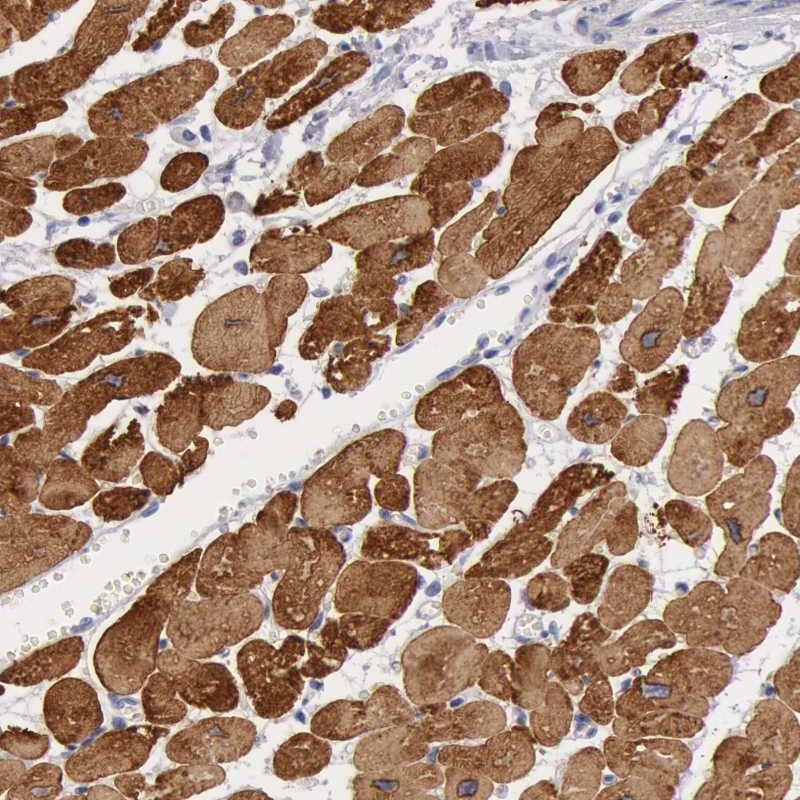

Immunohistochemical staining of human heart muscle shows strong cytoplasmic positivity in myocytes.